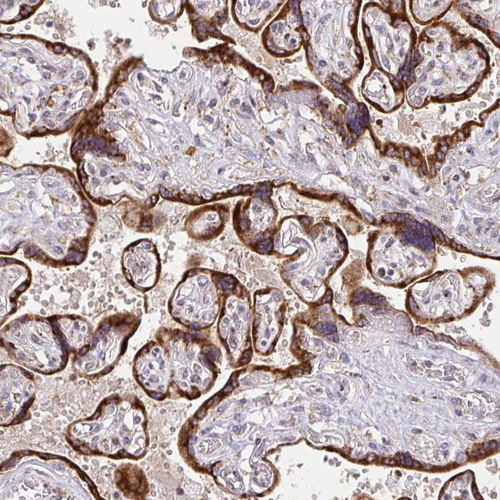

Immunohistochemical staining of human testis shows strong membranous and cytoplasmic positivity in cells in seminiferous ducts.